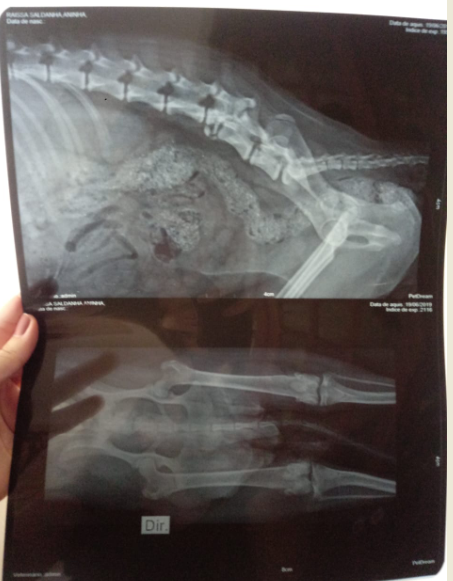

Oi, eu sou a Aninha! Fui atropelada quando estava nas ruas, e passei 3 semanas me arrastando na lama e nas chuvas até ser resgatada. Fui violentada por algum objeto que não sei dizer. Quebrei a coluna e preciso urgentemente me operar, para que possa ter a esperança de dias mais felizes, com ou sem carrinho. Preciso parar se sentir dor. Já sinto amor e segurança, fui resgatada e não volto pras ruas

ATUALIZAÇÃO - 25/06 Hoje faz uma semana que Aninha saiu das ruas, pelo olhar sensível da Tia Monara e do Tio Marcos. Ela não tem mais pulgas e carrapatos, esta vermifugada, come bem. Fez exames e descobriu que quebrou a coluna, precisará de cirurgia para estabilizá-la e reduzir as dores. Usará fraldas, por enquanto não controla o cocô e o xixi. Mas já está fazendo os dois bem, não precisará mais de lavagem, se Deus quiser. Essa semana repetiremos o hemograma, para ver se as taxas melhoraram, e continuaremos tentando organizar a cirurgia. Nada disso é tão importante em saber que, em uma semana, ela se arrasta pela casa toda, adora ficar junto de Luiz, melhora gradualmente a sua relação com Tapi (que continua desconfiada 😂) , vai comer e beber água sozinha, reconhece todo mundo, e vai receber a gente na porta quando chegamos 💝 Ajude Aninha a melhorar a sua qualidade de vida! Se voce puder, contribua na vaquinha virtual. E compartilhe, no insta, no Whatsapp da família, dos amigos. Ela merece ser feliz!

Oi pessoal! Meus dias tem sido intensos, cheios de novidades! Depois da transfusão dei uma melhorada e fiquei um pouco mais disposta! Comecei a conhecer o mundo, fui passear, conheci o parcão, a praia e a casa do vovô. Fiquei feliz demais! Mas infelizmente voltei a ter sangramento no xixi, e retornamos ao antibiótico. Estamos todos torcendo pra não ser uma nova infecção urinária forte! Essa semana preciso refazer o hemograma e tomar a segunda dose do Imizol. Se estiver tudo certo, e a anemia tiver melhorado, temos consulta com o ortopedista na semana que vem! Por enquanto, vou aproveitando o carinho e o cuidado de todo mundo. Já estou bem mais tranqüila com minha irmã canina, a Tapioca, e me sinto em casa! Me arrasto pelo apartamento, sei onde estão os brinquedos, e sou louca pelo mini humano. Estamos rezando pra que eu consiga fazer a operação, pare de sentir dor e possa finalmente começar a longa batalha de fisioterapia e acupuntura.